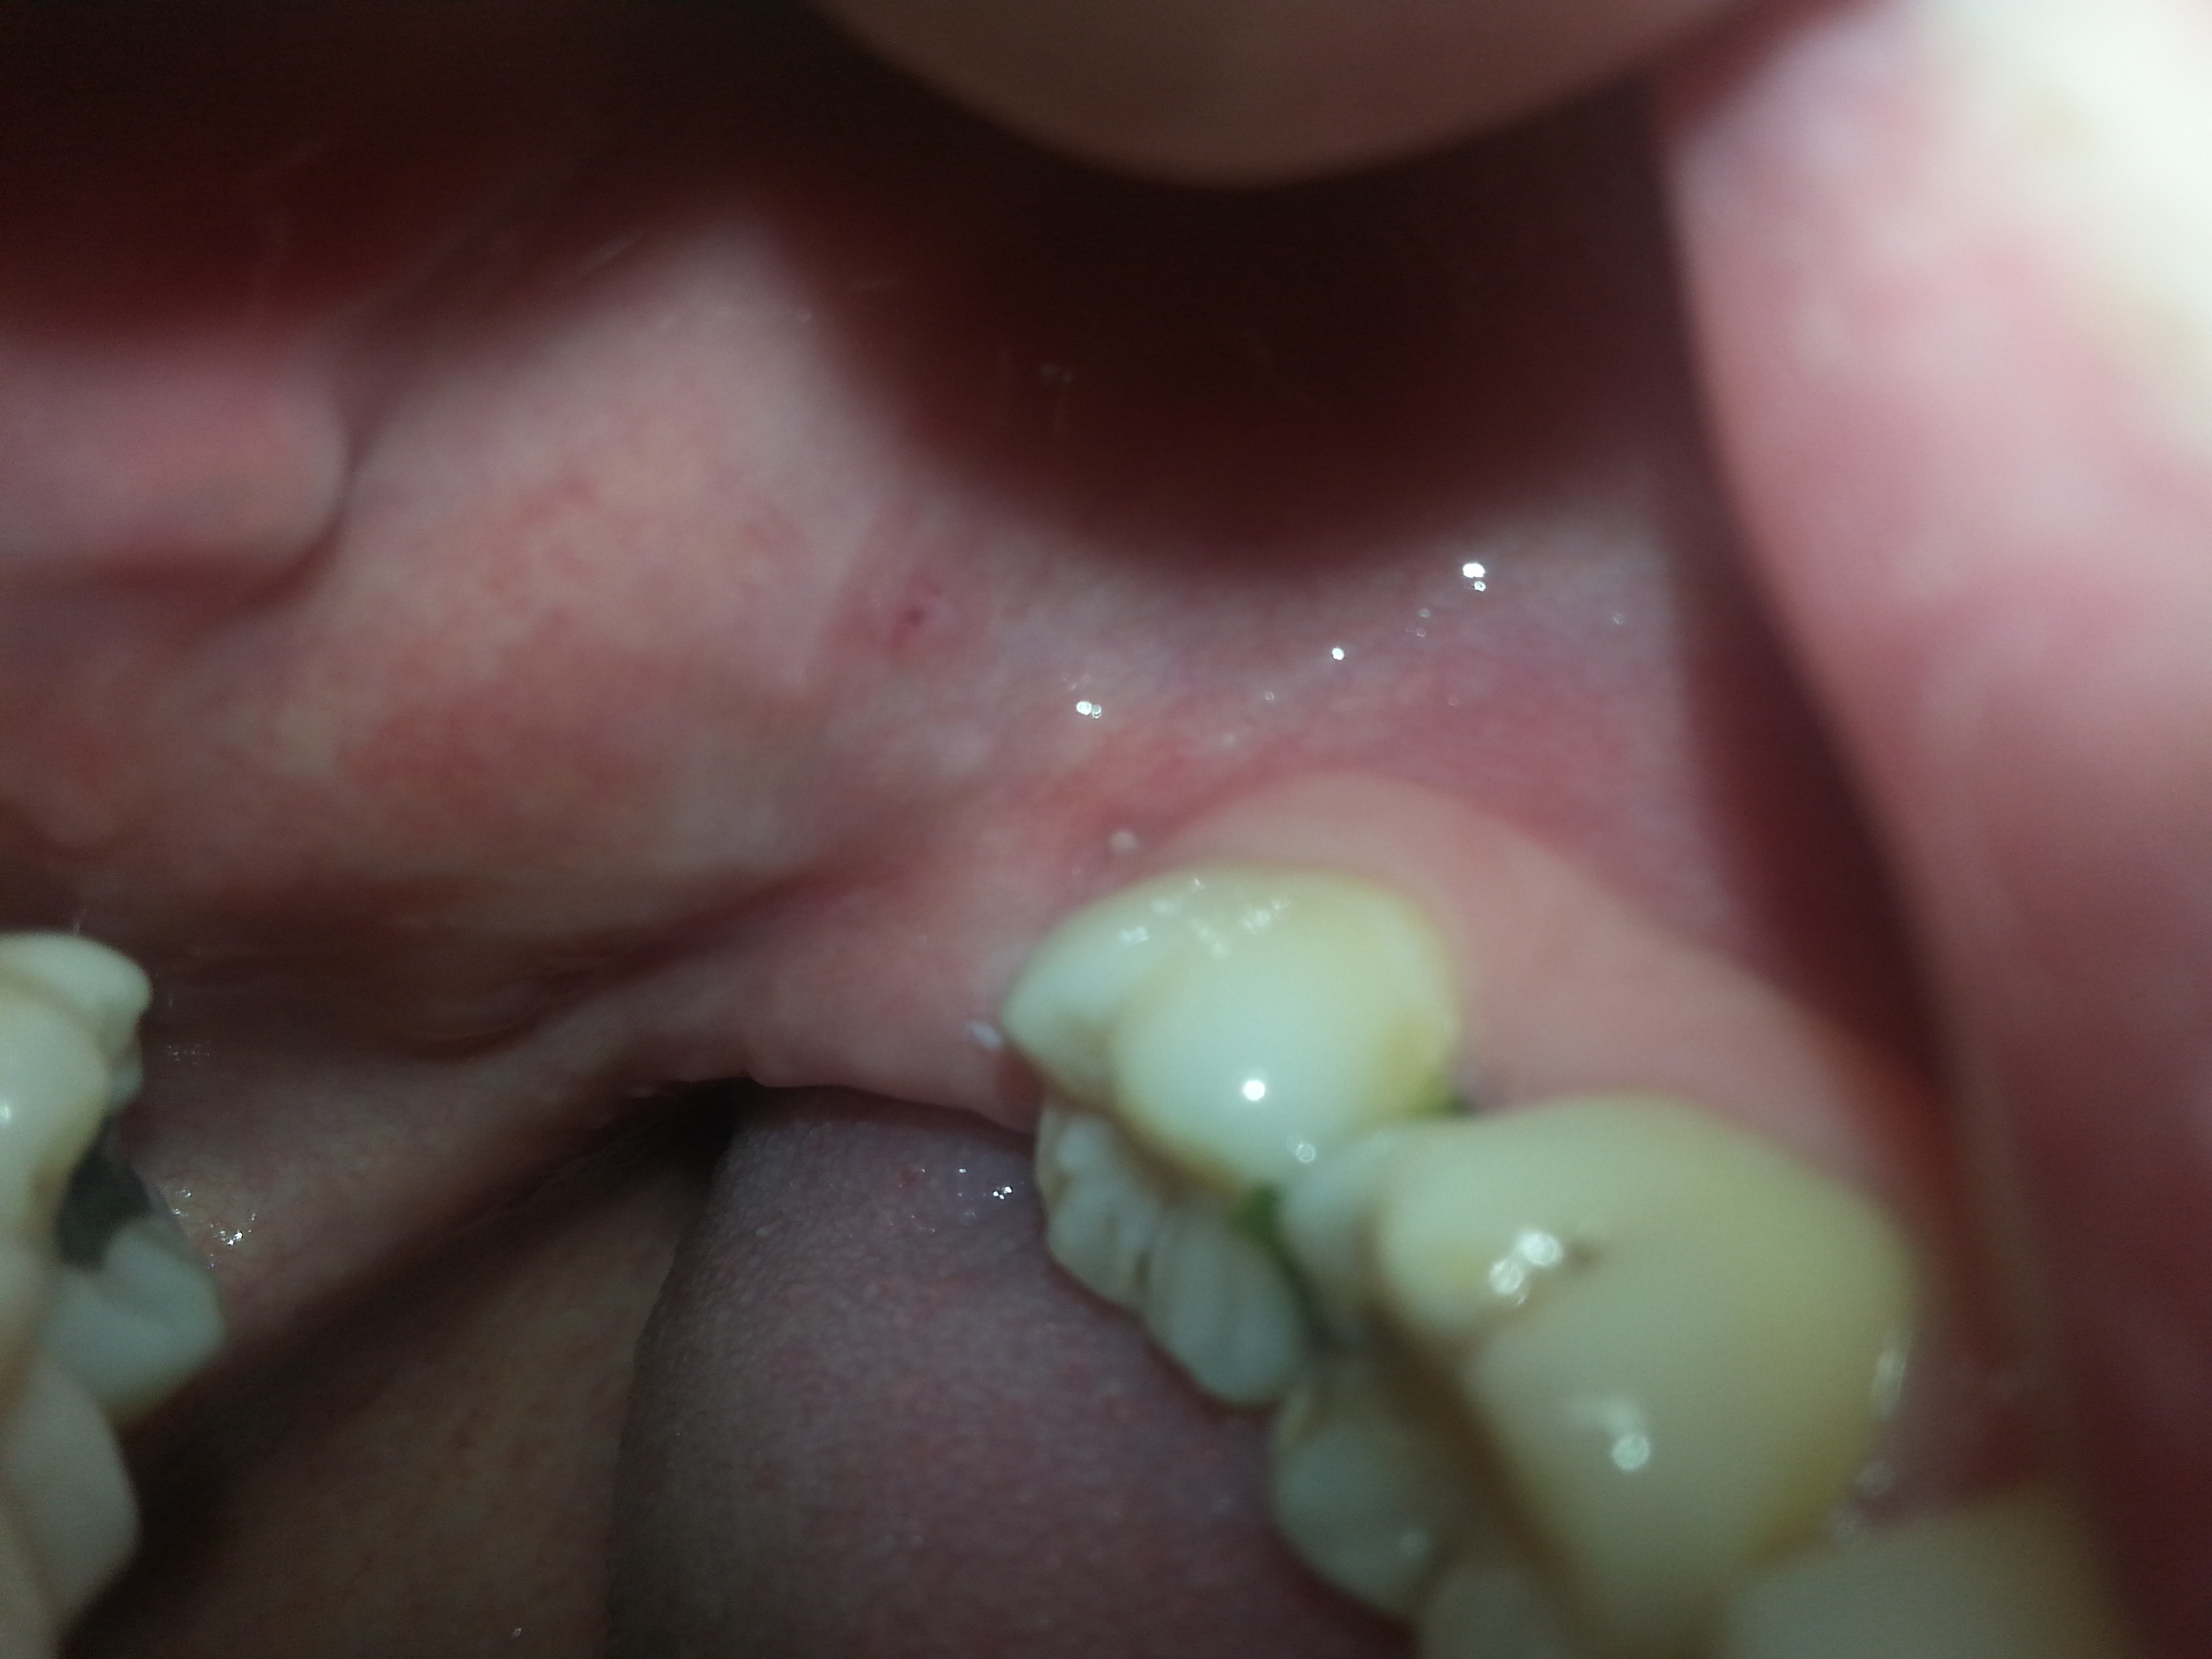

Am häufigsten bilden sich Wucherungen auf den Lippen, den Zungenseiten, dem Mundboden und am weichen Gaumen. Einige Wucherungen verursachen Schmerzen oder Reizungen. Die Wucherungen können vom Patienten selbst bemerkt oder bei einer Untersuchung entdeckt werden.

Fibrome, Erkrankungen der Speicheldrüsen oder Infektionen. EIne Ferndiagnose ist verständlicherweise nicht möglich. Wir empfehlen Ihnen daher eine Vorstellung bei einem Zahnarzt oder einem Mund-Kiefer-Gesichtschirurgen.

Schmerzloser Knubbel im Mund: Warzen, Zysten, Pilzinfektion und Co. Wenn Sie eine schmerzlose Wucherung im Mund entdecken, ist diese in den meisten Fällen gutartig. Oft handelt es sich um.

Bei der Mundschleimhautveränderung handelt es sich um eine pathologische Veränderung der Schleimhaut im Bereich der Zunge, Wange, des Gaumens oder des Kieferkammes. Es kann sich hierbei um Rauigkeiten, Erhabenheiten, Verhärtungen oder Verdickungen handeln. Auch Veränderungen der Farbe in Richtung rot oder weiß sind möglich.

Ein Wulst kann sich, als langsam wachsende runde Knochenhervorhebung in der Mitte des weichen Gaumens (Torus palatinus) oder auf dem Unterkiefer neben der Zunge bilden (Torus mandibularis). Diese harte Wucherung ist harmlos und weit verbreitet. Selbst große Wucherungen brauchen nicht behandelt zu werden, außer wenn die darüber liegende.